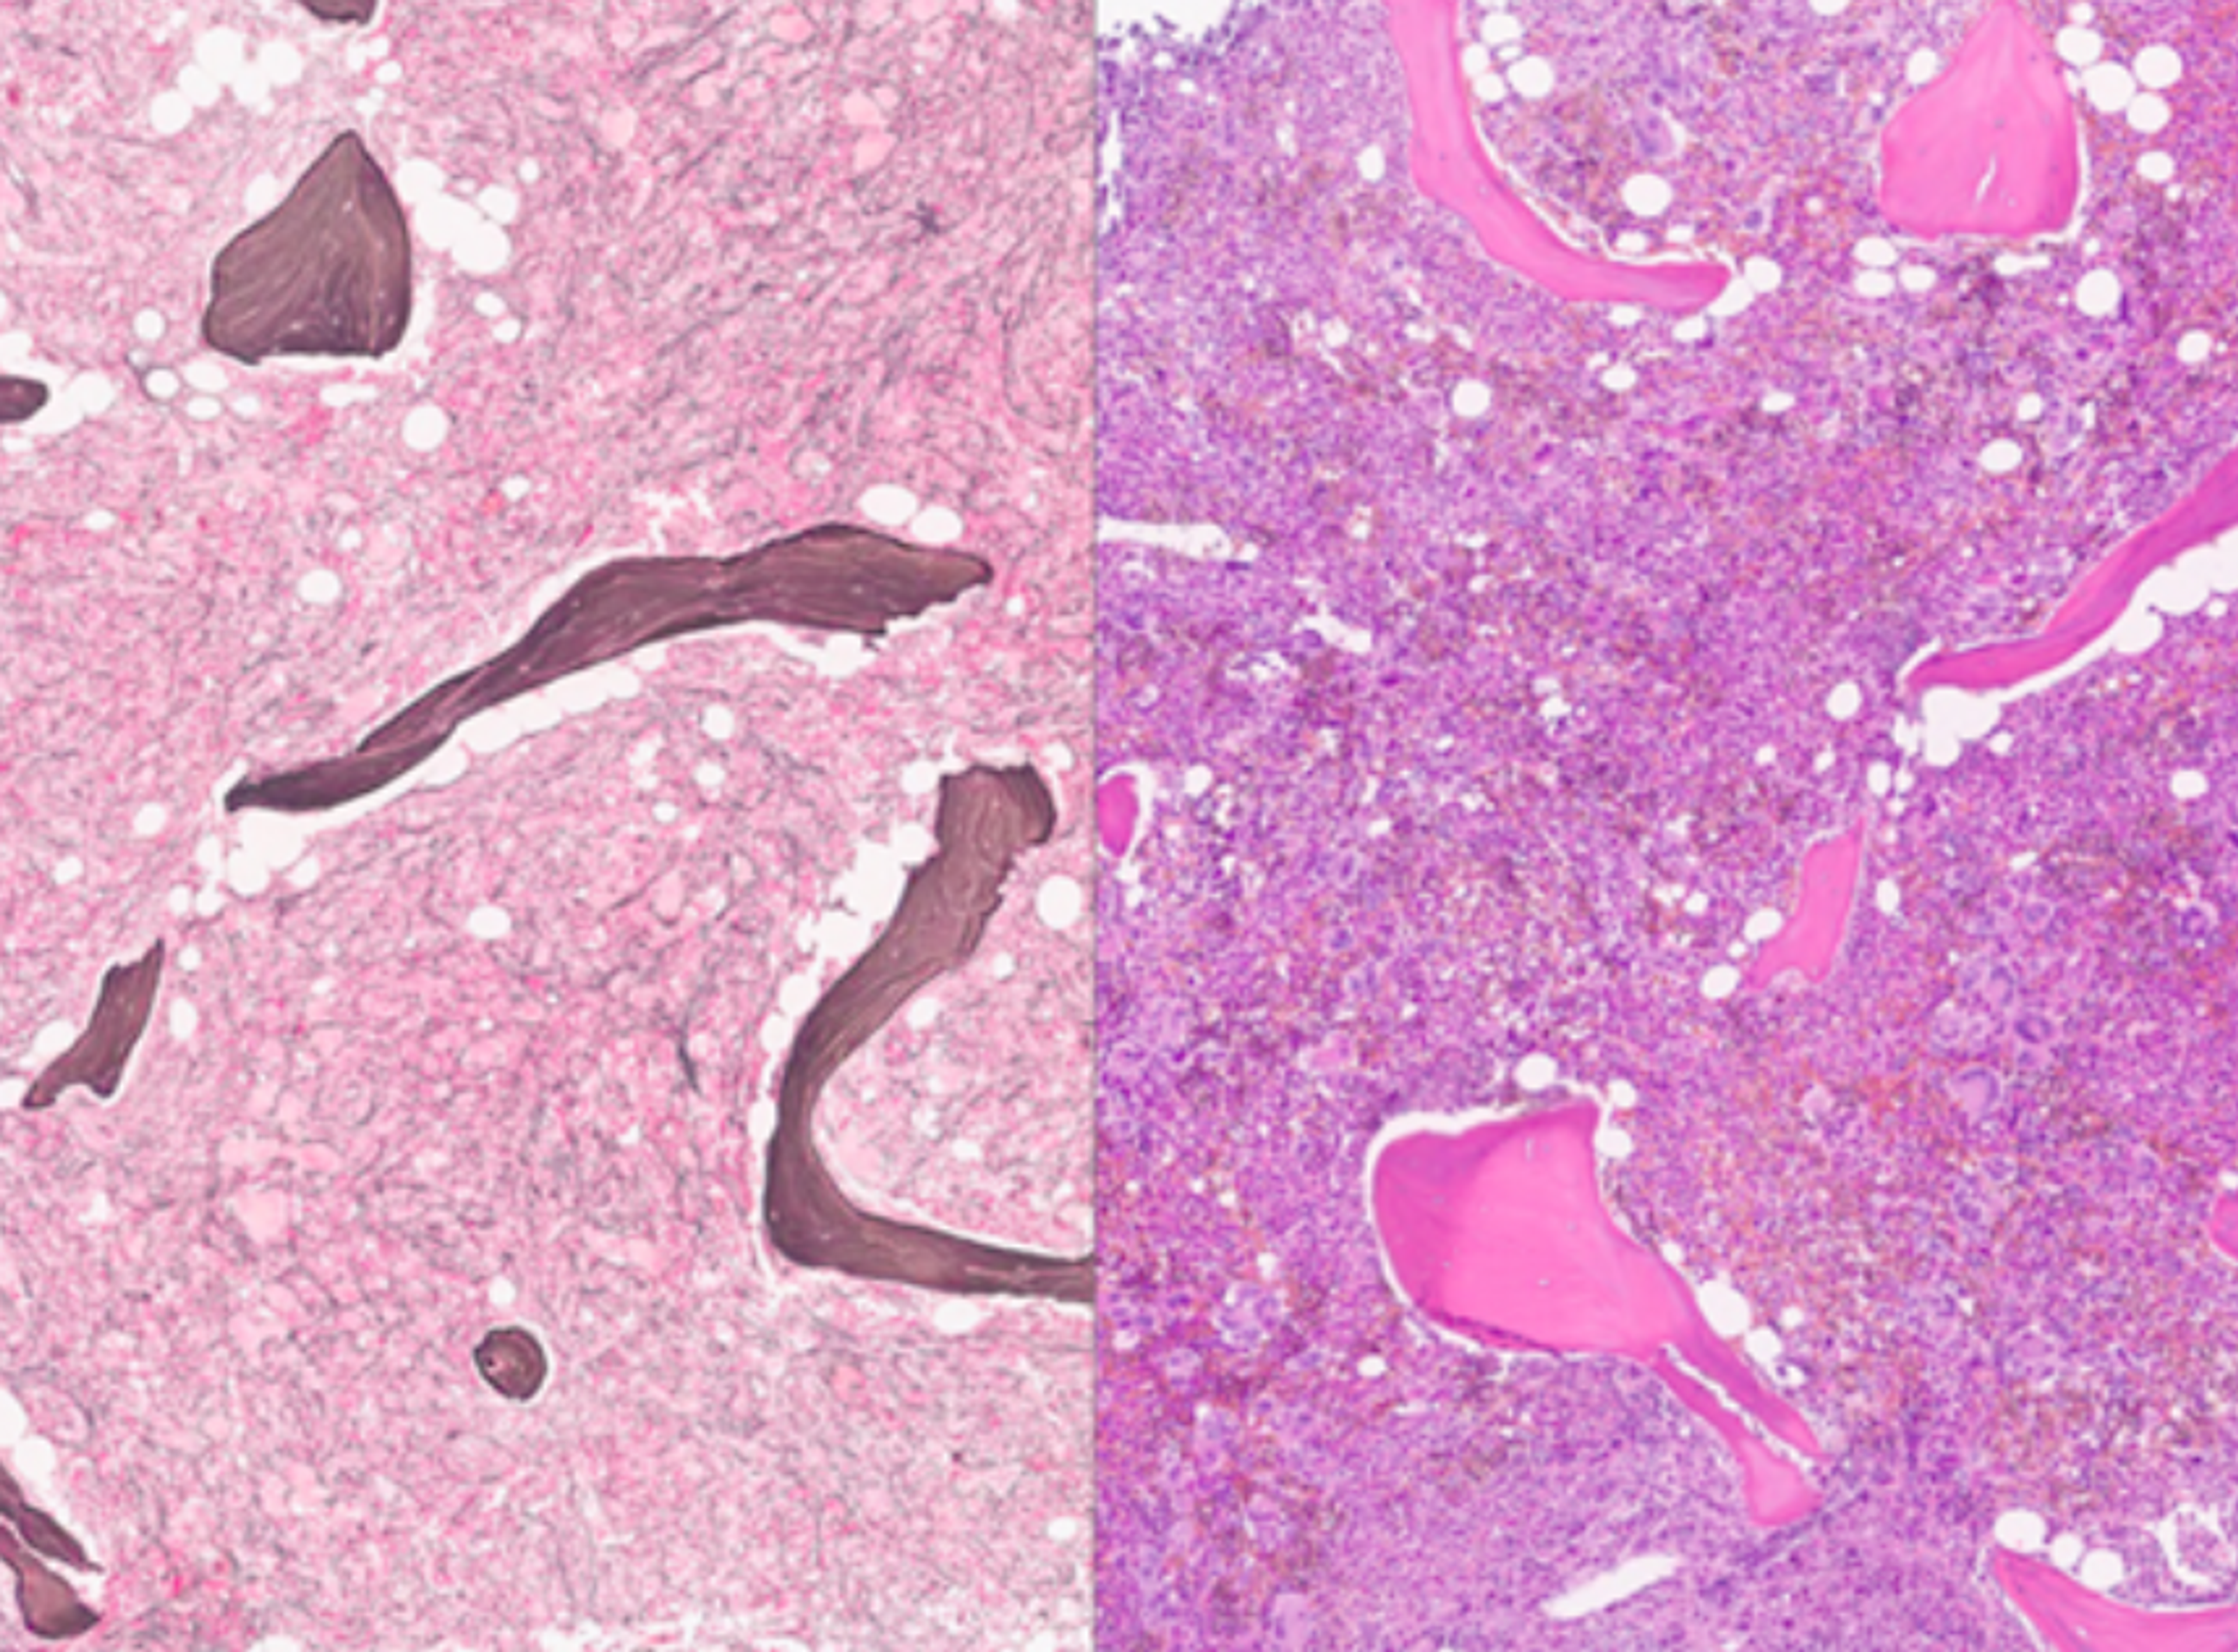

Molecular Pathology Laboratory Network, Inc. selects HALO AP to deliver comprehensive reference laboratory services and biopharma laboratory support

AI-powered solution to enhance diagnostic efficiency, streamline clinical trials, and improve patient outcomes across global pathology networks